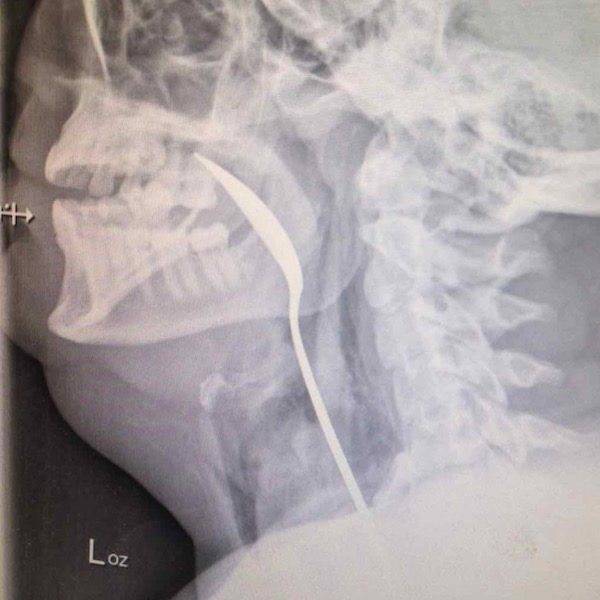

#17 Lusikka kurkussa